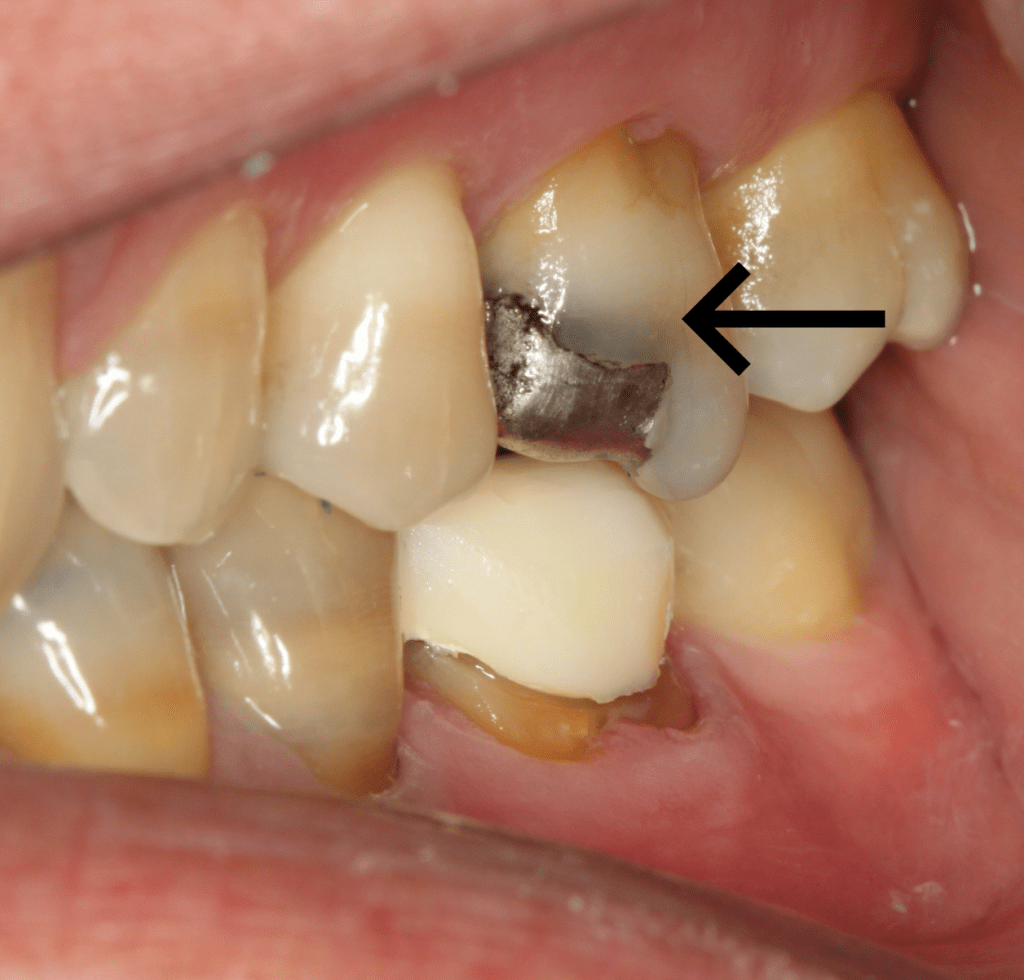

Amalgam has the ability to stain surrounding tooth structure by leaching corrosion products into the dentin tubules. The tooth may also be darker because of the dark filling and the translucent properties of a tooth. Elective replacement of the filling may be warranted for esthetic purposes.